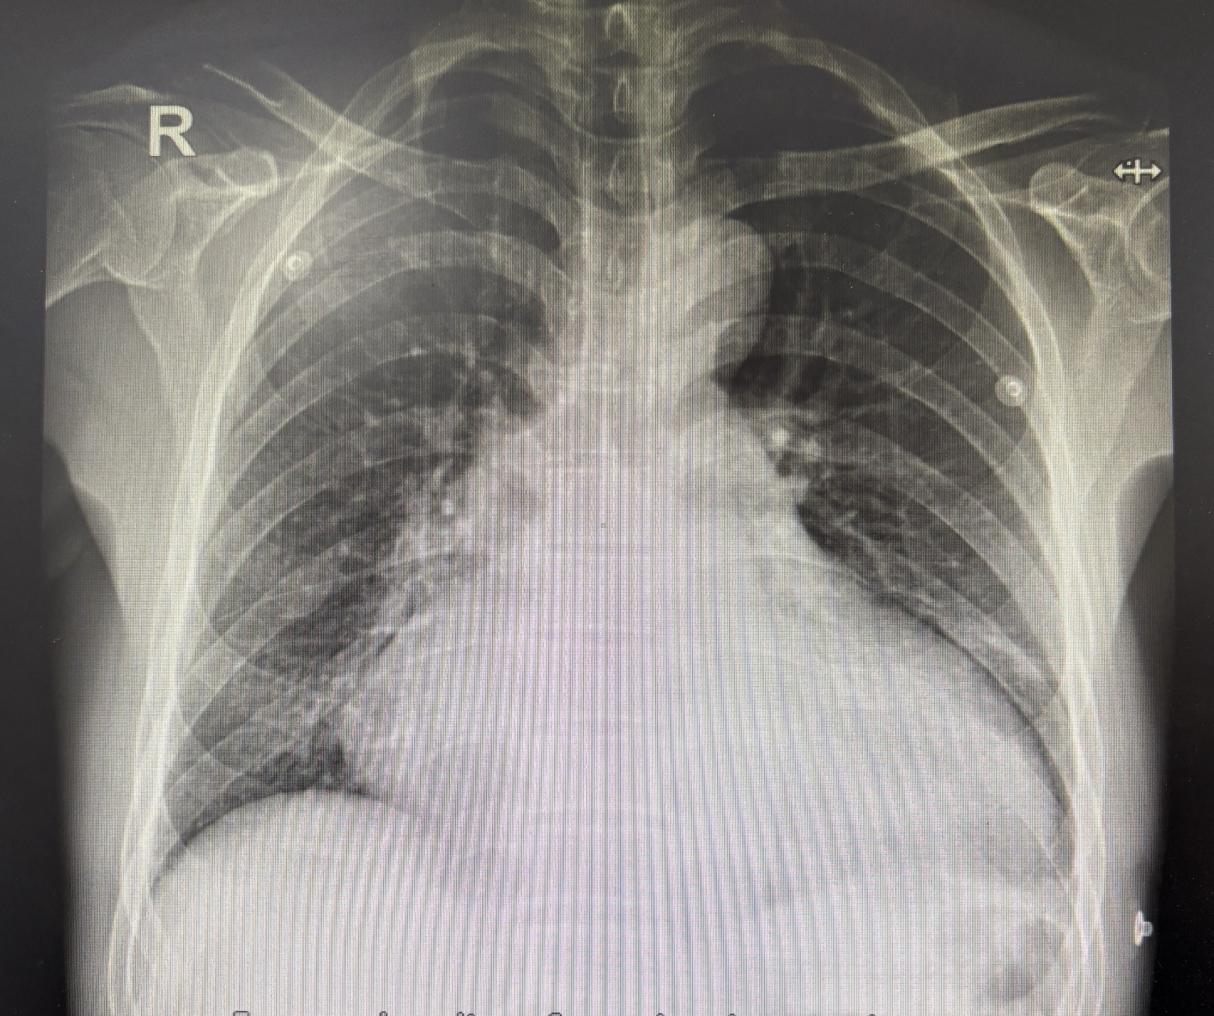

56岁的李先生,1月前无明显诱因间断出现活动后胸闷、气短,无胸痛咯血等其他不适,休息后有所好转,患者不以为然。近10天上述症状较前明显加重,出现不能平卧,颜面部水肿,咳嗽、咳白痰,这才让李先生跟他的家人引起重视。就诊于当地医院,心脏超声提示全心扩大,左心为著,主动脉窦部及升主动脉扩张,主动脉瓣、二尖瓣大量反流,肺动脉高压中度,当地医院诊断李先生为心脏联合瓣膜病、升主动脉瘤样扩张、肺动脉高压、急性心力衰竭、心功能IV级。由于患者心脏大、心功能太差,再加上正处于急性心衰阶段,外科手术风险极大,当地医院建议转至上级医院进一步治疗。李先生一家经多方了解,得知交大二院心外科高峰主任在高难度重症心脏病人的综合救治领域经验丰富,这无疑给一家人带来了生的希望。

入院后,高峰主任团队第一时间对李先生的病情进行分析、评估,患者主动脉窦部52mm,升主动脉内径42mm(正常成年人主动脉窦部内径为20-35mm,升主动脉直径小于35mm),LV前后径舒张期末80mm(在医学上,左心室超过70mm即是巨大左心室),LVEF(左心室射血分数)只有0.38。一方面,主动脉窦瘤有破裂风险,需尽快手术拆除炸弹;另一方面,患者左心室巨大,心功能差,手术风险和死亡率明显增加。生死关头,到底该如何抉择?整个心外团队经过深入研究,为李先生制定了一套专属的诊疗方案,在保证手术安全的前提下,以最快的速度纠正心衰、安排手术。凭借着团队的实力和精心的准备,以严苛的标准做好每个环节,高峰主任仅用短短3小时就完成了心脏复杂的高难度手术(Bentall手术+二尖瓣机械瓣置换术),术后患者安返心外科监护室。